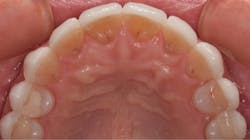

By carefully removing the veneers with fine diamond burs in a high-speed handpiece with water spray, I was able to minimize additional tooth structure removal, and no anesthetic was needed. Figure 3 shows the facial view after removal of the veneers. The incisal view can be seen in Figure 4. The patient decided that she wanted two additional veneers for her second premolars. Final impressions were taken, as well as a facebow record and occlusal registration. The patient chose Vita OM2 bleach shade as her desired color.

Figure 4: Incisal view after removal of the veneers